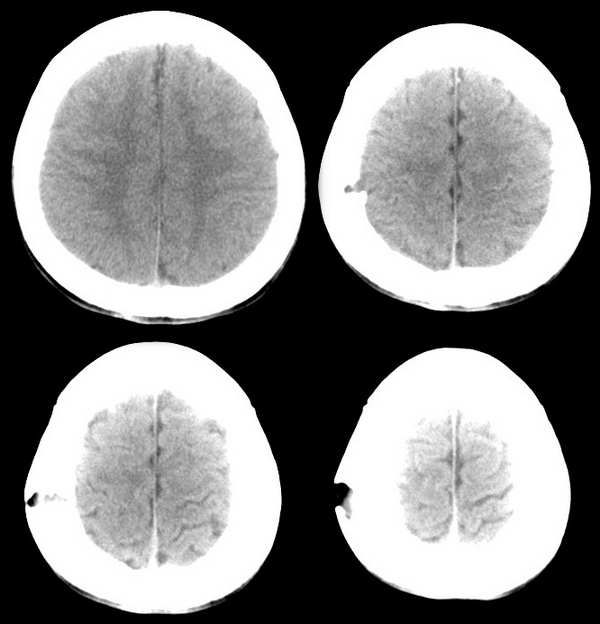

以下是引用wawaquan回复:mri0263:顶骨病变,在2006-1-1 23:13:00的发言:[br]首先考虑:嗜酸性肉芽肿。嗜酸性细胞肉芽肿是一种病因不明、往往发生于外伤后的全身性骨病。好发于儿童和20岁左右的青年,男性较女性多见。除指骨和趾骨外全身各扁平骨均可发病。颅骨为好发部位,病变多为单发,约占70 ̄85%。病理在镜下可见多种细胞成份,包括淋巴细胞、网状细胞、嗜酸性细胞、多核细胞、纤维母细胞、浆细胞等。其发展分四个阶段:(1)增殖期;(2)肉芽期;(3)黄色肿块期;(4)纤维化期。起病初时常有低热、局部肿胀疼痛。本病主要以手术治疗为主,术后加用放疗。单发者预后较佳。 [症状体症] 1.发病初期常有低热、乏力、食欲不振等症状。2.外伤后或突然出现头部疼痛性肿块,病变可为单发或多发。3.累及肋骨、股骨和骨盆等骨骼而出现胸痛、骨盆疼痛和病理性骨折。 [诊断依据] 1.常见于青少年,可有外伤史,头部局限性肿块,轻微疼痛,生长缓慢,常位于顶骨、枕骨及颞骨。2.起病初期可出现低热、乏力、食欲不振等症状。3.查血象白细胞增多和嗜酸性细胞增多,血沈加快。4.头颅x线片显示局部颅骨缺损,呈园形或椭园形,边界整齐清楚,无硬化,身体其他部位扁平骨也可能有类似病变。5.病理活检确诊。 [治疗原则] 1.手术切除肿块,颅骨缺损范围大者,可同期行颅骨修补术。2.范围大,多发者,行放射治疗。 [疗效评价] 1.治愈:肿块消失,症状消失或明显好转,颅内压正常。2.好转:肿块缩小,症状缓解或稳定。3.未愈:肿块增大或未变,颅内压增高,症状加重。 [专家提示] 本病为颅骨肉芽肿性病变,表现为颅骨破坏,取代之为软性肿块,部分病人发生于外伤后。因其起病初期症状轻,往往被部分病人忽略,如出现头部轻微痛性肿块,尤其伴有其他部位骨骼症状者,应及时找有关专科医师就诊。确诊需病理活检。目前尚无一种药物对本病有特效。治疗主要采取手术切除肿块,术后加用放疗,也可单独用放疗。单发者预后良好。 [br][br][br][本贴已被 wawaquan 于 2006-1-1 23:34:10 修改过]

以下是引用jiajie在2006-3-4 19:54:00的发言:[br]孤立、略膨胀、穿凿样、形态不规则、边缘有硬化,考虑嗜酸性肉芽肿。[br][quote]以下是引用wawaquan回复:mri0263:顶骨病变,在2006-1-1 23:13:00的发言:[br]首先考虑:嗜酸性肉芽肿。嗜酸性细胞肉芽肿是一种病因不明、往往发生于外伤后的全身性骨病。好发于儿童和20岁左右的青年,男性较女性多见。除指骨和趾骨外全身各扁平骨均可发病。颅骨为好发部位,病变多为单发,约占70 ̄85%。病理在镜下可见多种细胞成份,包括淋巴细胞、网状细胞、嗜酸性细胞、多核细胞、纤维母细胞、浆细胞等。其发展分四个阶段:(1)增殖期;(2)肉芽期;(3)黄色肿块期;(4)纤维化期。起病初时常有低热、局部肿胀疼痛。本病主要以手术治疗为主,术后加用放疗。单发者预后较佳。 [症状体症] 1.发病初期常有低热、乏力、食欲不振等症状。2.外伤后或突然出现头部疼痛性肿块,病变可为单发或多发。3.累及肋骨、股骨和骨盆等骨骼而出现胸痛、骨盆疼痛和病理性骨折。 [诊断依据] 1.常见于青少年,可有外伤史,头部局限性肿块,轻微疼痛,生长缓慢,常位于顶骨、枕骨及颞骨。2.起病初期可出现低热、乏力、食欲不振等症状。3.查血象白细胞增多和嗜酸性细胞增多,血沈加快。4.头颅x线片显示局部颅骨缺损,呈园形或椭园形,边界整齐清楚,无硬化,身体其他部位扁平骨也可能有类似病变。5.病理活检确诊。 [治疗原则] 1.手术切除肿块,颅骨缺损范围大者,可同期行颅骨修补术。2.范围大,多发者,行放射治疗。 [疗效评价] 1.治愈:肿块消失,症状消失或明显好转,颅内压正常。2.好转:肿块缩小,症状缓解或稳定。3.未愈:肿块增大或未变,颅内压增高,症状加重。 [专家提示] 本病为颅骨肉芽肿性病变,表现为颅骨破坏,取代之为软性肿块,部分病人发生于外伤后。因其起病初期症状轻,往往被部分病人忽略,如出现头部轻微痛性肿块,尤其伴有其他部位骨骼症状者,应及时找有关专科医师就诊。确诊需病理活检。目前尚无一种药物对本病有特效。治疗主要采取手术切除肿块,术后加用放疗,也可单独用放疗。单发者预后良好。 [br][br][br][本贴已被 wawaquan 于 2006-1-1 23:34:10 修改过]